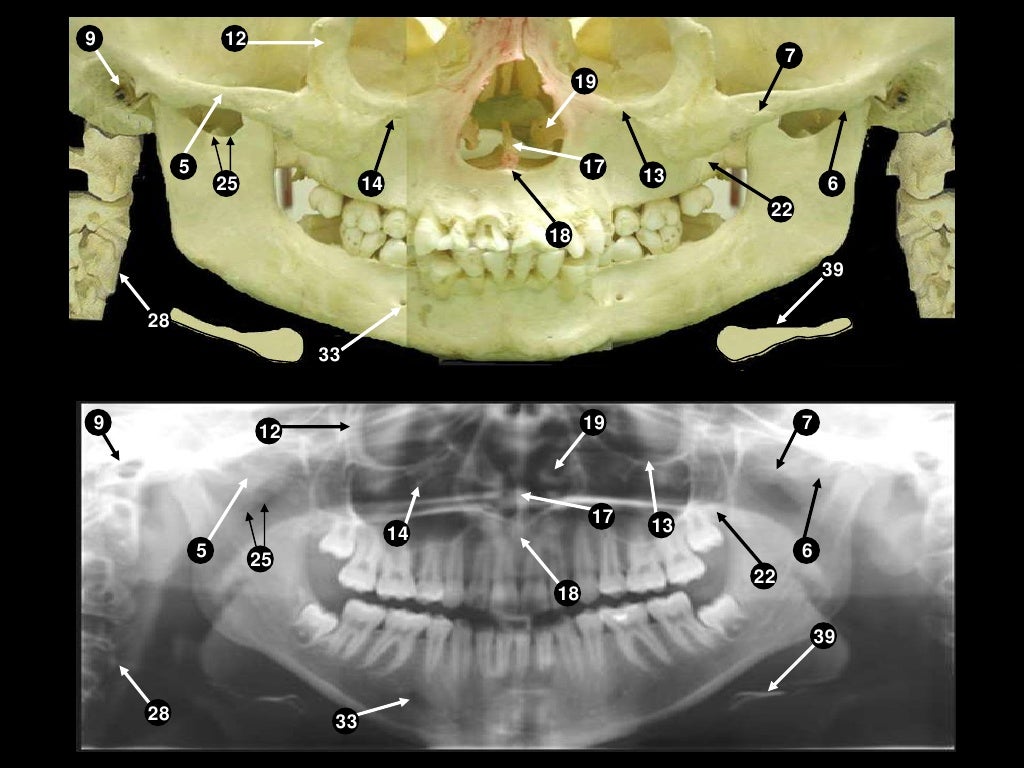

Radiographic AnatomyPAN Diagram Quizlet Pan- Definition Anatomy Prefix meaning all, entire (properly affixed to words derived from g. 110 rows understanding medical words: They help to avoid any ambiguity that can arise when describing the location of. Here is a list of word parts. Word parts and what they mean. Identify three planes most commonly used in the study of anatomy. It’s a complex assemblage of bones. Pan- Definition Anatomy.